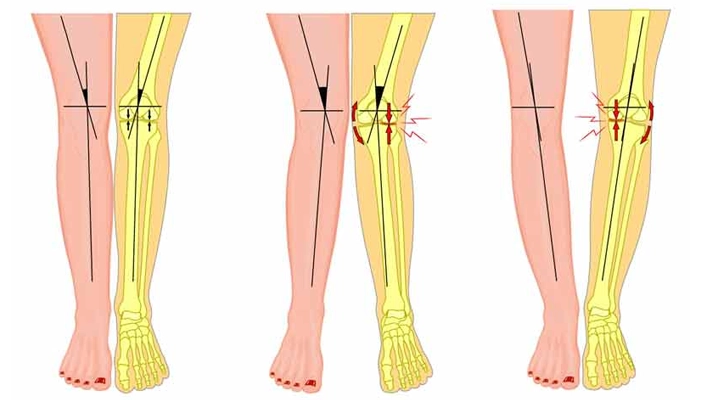

✅ ۱. شدت انحراف و پیچیدگی عمل

میزان انحراف پا و اینکه آیا هر دو پا نیاز به جراحی دارند یا فقط یکی، نقش مهمی در مبلغ جراحی پای پرانتزی دارد. هرچه اصلاح بیشتری نیاز باشد یا جراحی دوطرفه باشد، هزینه بالاتر خواهد بود.